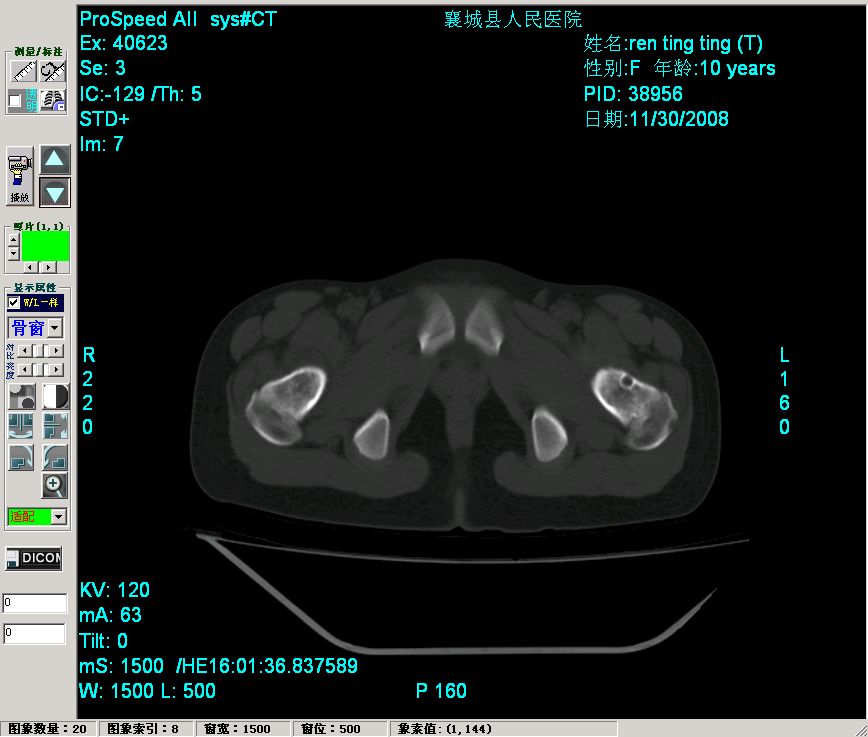

女,10岁,右髋不适3个月。拍片及ct示,股骨颈环状低密度区,边缘硬化,看看是软骨岛或股骨颈疝凹。

单从这两张片子上不能分别二者吧,建议发ct片

异常低密度囊状影在左股骨颈,而介绍病史说右髋不适......到底哪一侧?

翁:ct上传毕。